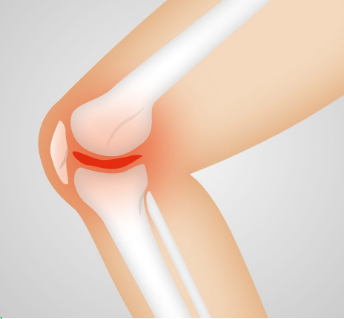

슬개대퇴증후군은 슬개골과 대퇴골의 밀접한 관련성에서 시작되는 질환입니다. 슬개골은 무릎을 굽히거나 펼 때 대퇴골의 여러 면과 닿아 있습니다. 만약 이 두 뼈가 잘 맞물리지 않은 경우에는 ‘찌릿찌릿’ 아픈 통증이 느껴집니다. 뼈가 엇갈리게 닿게되면서, 그리고 주위의 인대도 다른 방향으로 당겨 통증을 유발시키기 때문입니다. 산을 내려오거나, 쪼그려 앉기, 무릎 꿇은 자세 등 무릎에 부하를 많이 주는 신체 동작의 경우에 증상이 나타납니다.

무릎 연골연화증은 무릎뼈를 감싸고 있는 연골이 부드러워지거나 약해지면서 탄력을 잃고 충격을 이기지 못하고 손상되는 질환을 말합니다. 초기 당시에는 단순한 염증으로 시작되는 질환이지만 점차 연골 전체 부분에 균열로 이어져 뒤 손상 단계로 진행돼 무릎의 기능을 떨어뜨리게 됩니다.

슬개대퇴증후군과 연골연화증의 예방을 위해서는 오랜시간 앉거나 다리를 꼬는 자세 그리고 무릎을 꿇는 자세를 피해야 합니다. 이어서 운동 전후로 적절한 스트레칭을 통해 무릎 주변 근육을 부드럽게 해주는 것이 좋다. 특히나 근력과 유연성 운동이 중요합니다. 근육이 무릎 관절을 잡아주는 기능을 하여 연골에 가해지는 압력을 줄여주는 허벅지 근육강화 운동이 무릎질환 예방에 도움이 됩니다.